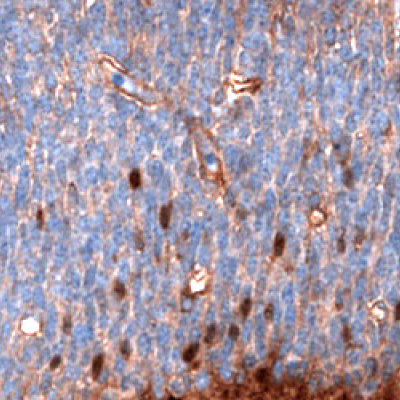

ALDH1A3

The aldehyde dehydrogenases ALDH1A3 are associated with cell adhesion and tumor invasion and are a marker of the Mes-subtype of gliomas. ALDH is a marker of cancer stem cells associated with the malignant phenotype in gliomas. Among the ALDH isoforms, ALDH1A3 is overexpressed in high-grade gliomas compared to low-grade gliomas, while ALDH1A1 is overexpressed in low-grade gliomas compared to high-grade gliomas. Most of the Mes-subtypes have high ALDH1A3 mRNA expression, indicating ALDH1A3 as a useful marker for the Mes-subtype of gliomas.24

Figure 8 shows immunostainings of EZH2, PARP1, and ALDH1A3 expression in various sample types.

Figure 8A.Multiplexed IHC-IF staining of human glioblastoma using the Anti-EZH2 monoclonal (nuclear, in green), the Anti-PARP1 monoclonal (nuclear, in red), and the Anti-ALDH1A3 monoclonal (cytoplasmic, in blue) antibodies.

Figure 8B.Multiplexed IHC-IF staining of human astrocytoma samples using the Anti-EZH2 monoclonal (nuclear, in green), the Anti-PARP1 monoclonal (nuclear, in red), and the Anti-ALDH1A3 monoclonal (cytoplasmic, in blue) antibodies.

Figure 8C.Multiplexed IHC-IF staining of human oligodendrocytoma samples using the Anti-EZH2 monoclonal (nuclear, in green), the Anti-PARP1 monoclonal (nuclear, in red), and the Anti-ALDH1A3 monoclonal (cytoplasmic, in blue) antibodies.

Figure 8D.Multiplexed IHC-IF staining of human normal cortex samples using the Anti-EZH2 monoclonal (nuclear, in green), the Anti-PARP1 monoclonal (nuclear, in red), and the Anti-ALDH1A3 monoclonal (cytoplasmic, in blue) antibodies.